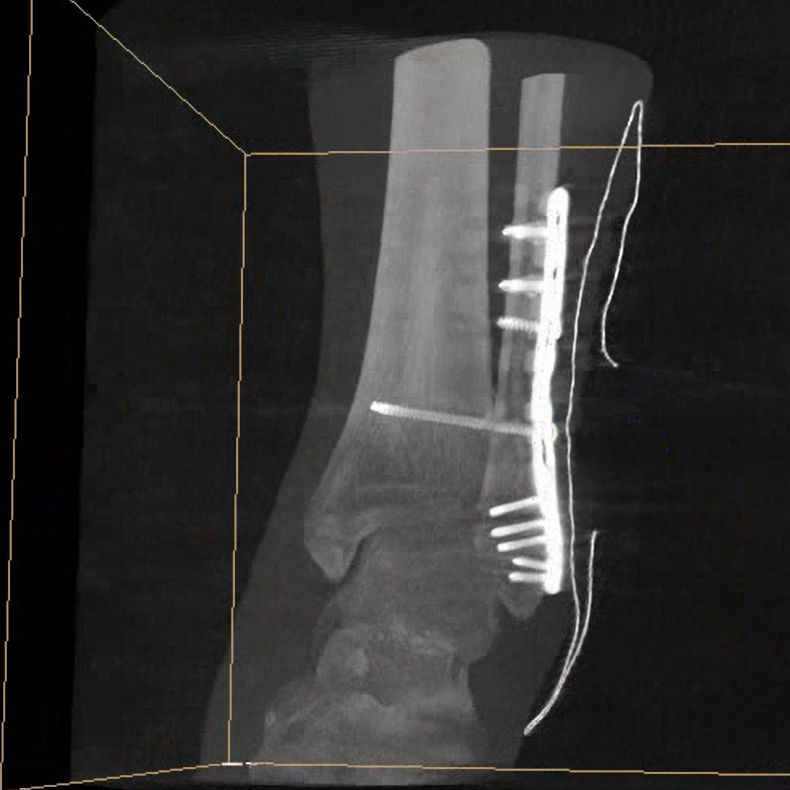

術中三維成像和橫斷面圖像提供多角度的手術診斷信息,輔助醫生進行術中評估判斷,諸如骨折復位情況和內植入螺釘的尺寸和位置,輔助手術更好地完成。

在C臂掃描過程中,始終保持拍攝主體處于射線束的中心,避免了序列圖像采集過程中的橫縱方向運動,減少相對運動造成的運動偽影。

平板垂直升降運動 便于術中微調平板與拍攝主體的距離,更加貼近病灶體,成像范圍更大,圖像更清晰。